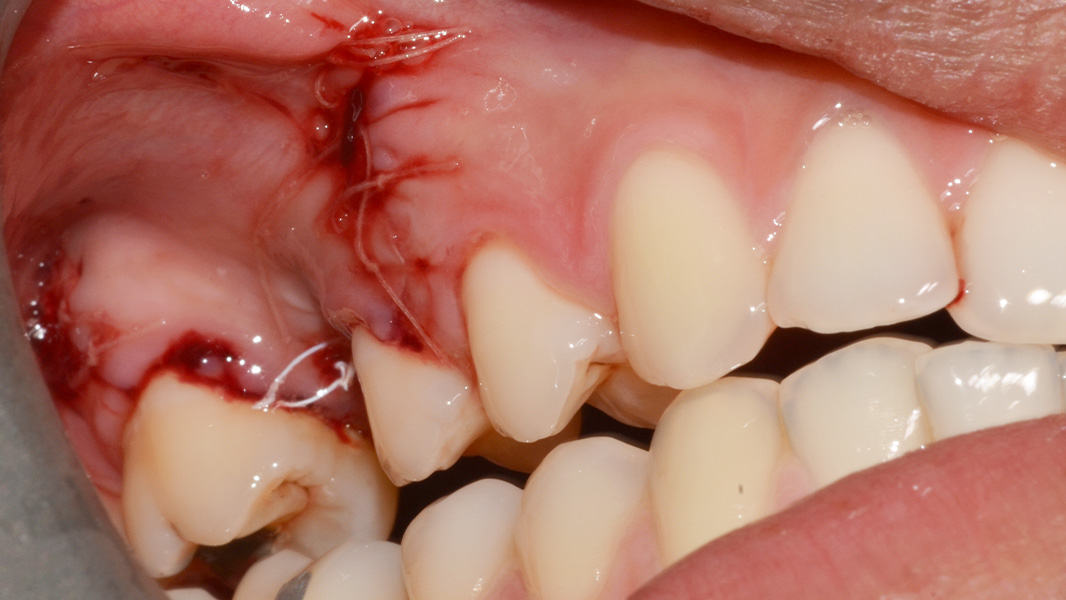

Die transgingivale Einheilung dentaler Implantate ist ein wissenschaftlich gut untersuchtes und klinisch erfolgreiches Verfahren. Für die transgingivale Einheilung sollten die Implantate primärstabil inseriert werden, nur kleine Hartgewebeaugmentationen notwendig sein und ausreichend stabiles Weichgewebe vorliegen. Um in Fällen mit Augmentationsbedarf das iSy Implantatsystem verwenden zu können – ohne die Implantatbasis demontieren zu müssen – bietet das iSy System Implantate mit gestecktem Einbringpfosten an. Nach gedeckter Einheilung und Freilegung des Implantats können drei verschieden breite Gingivaformer eingebracht und im Anschluss sowohl eine digitale als auch konventionelle Abformung durchgeführt werden. Die entsprechenden Abformpfosten und Esthomic Abutments gibt es ebenfalls in drei verschiedenen Emergenzprofilen, welche formkongruent zu den Gingivaformern sind. Im folgenden Fall wurde ein geringes bukkales Knochendefizit mit einem Gemisch aus Eigenknochen und PRF (Plättchenreiches Fibrin) augmentiert und das Weichgewebedefizit mit einer azellulären dermalen Matrix (NovoMatrix/ BioHorizons) aufgebaut.

Nicht nur die korrekte dreidimensionale Positionierung der Implantate, sondern auch das Know-how der Knochenaugmentation und die entsprechende Manipulation des Weichgewebes sind essenziell für den Erfolg. Die Kieferknochenrekonstruktion mit autologen Knochenblöcken, die nach der Beschreibung von Prof. Dr. F. Khoury ausgedünnt werden, sowie das Auffüllen der entstandenen Hohlräume mit autologen Knochenspänen führen zu einem vorhersagbaren, langzeitstabilen laminären Knochen. Auch das Implantatdesign mit der parallelwandigen Schulter sowie das Platform-Switching tragen maßgeblich zur erfolgreichen Rekonstruktion bei. Ein weiterer Vorteil des iSy Implantatkonzepts ist die Implantatbasis. Bei transgingivaler Einheilung verbleibt sie bis zur endgültigen Versorgung auf dem Implantat. Die Manipulation des Weichgewebes durch häufigen Abutmentwechsel hat laut Studien einen beachtlichen Anteil an Knochen- und Weichgewebsveränderungen. Auch bei gedeckter Einheilung werden ab dem Zeitpunkt der Freilegung mithilfe der Implantatbasis Abutmentwechsel minimiert.